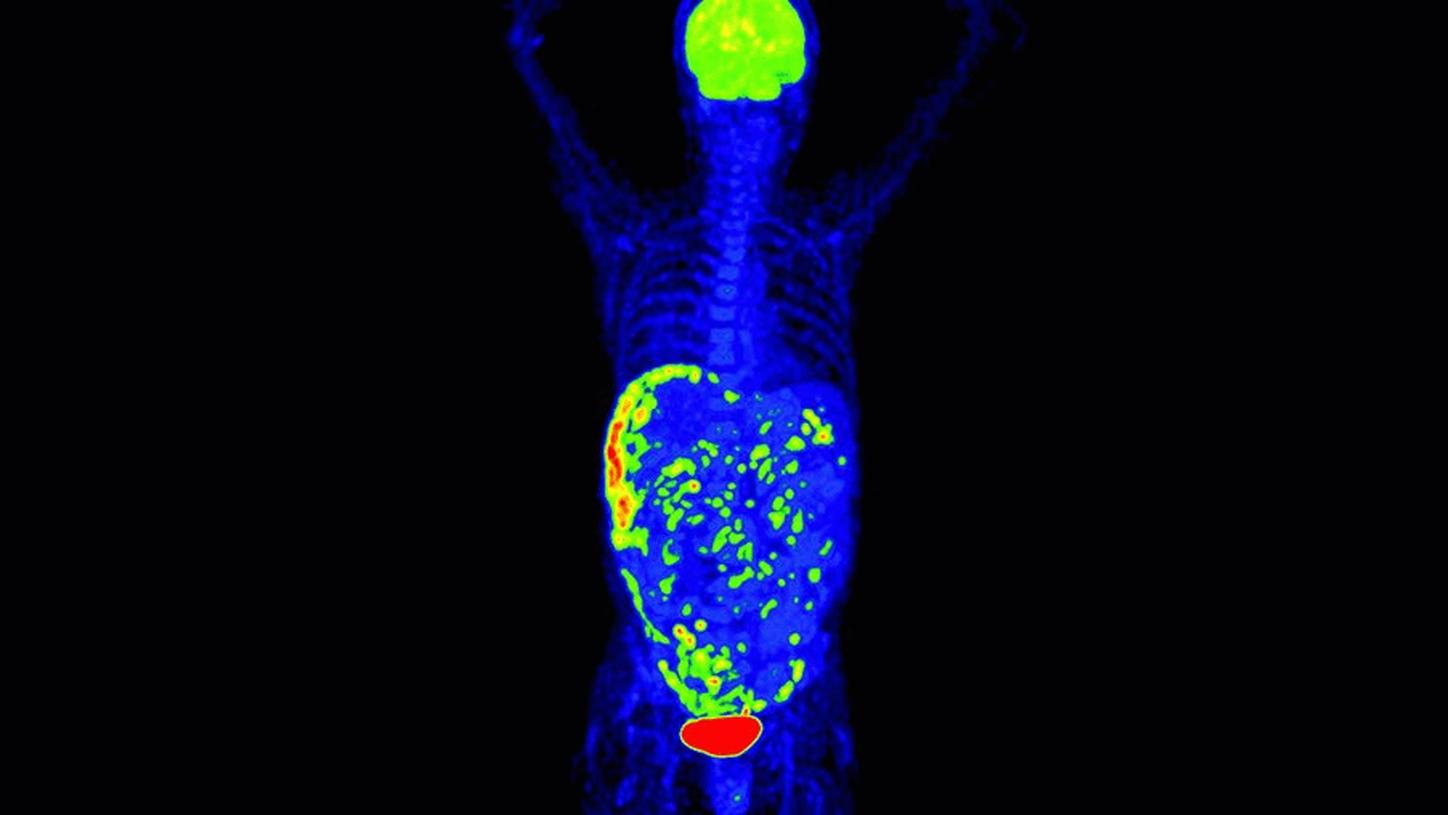

Answering to clinical needs in oncology, neurology, cardiology, and radiology, Siemens Healthineers Molecular Imaging systems provide PET/CT, SPECT, and hybrid SPECT scanner (SPECT/CT) solutions to help clinicians diagnose, treat, and monitor diseases more confidently.